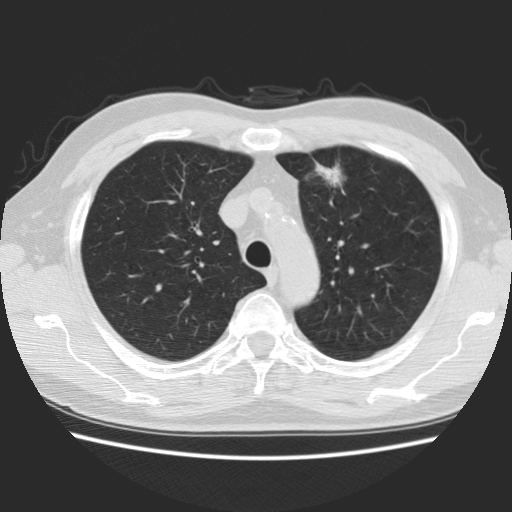

Choose if image shown above is Real or Fake :

Real

Fake